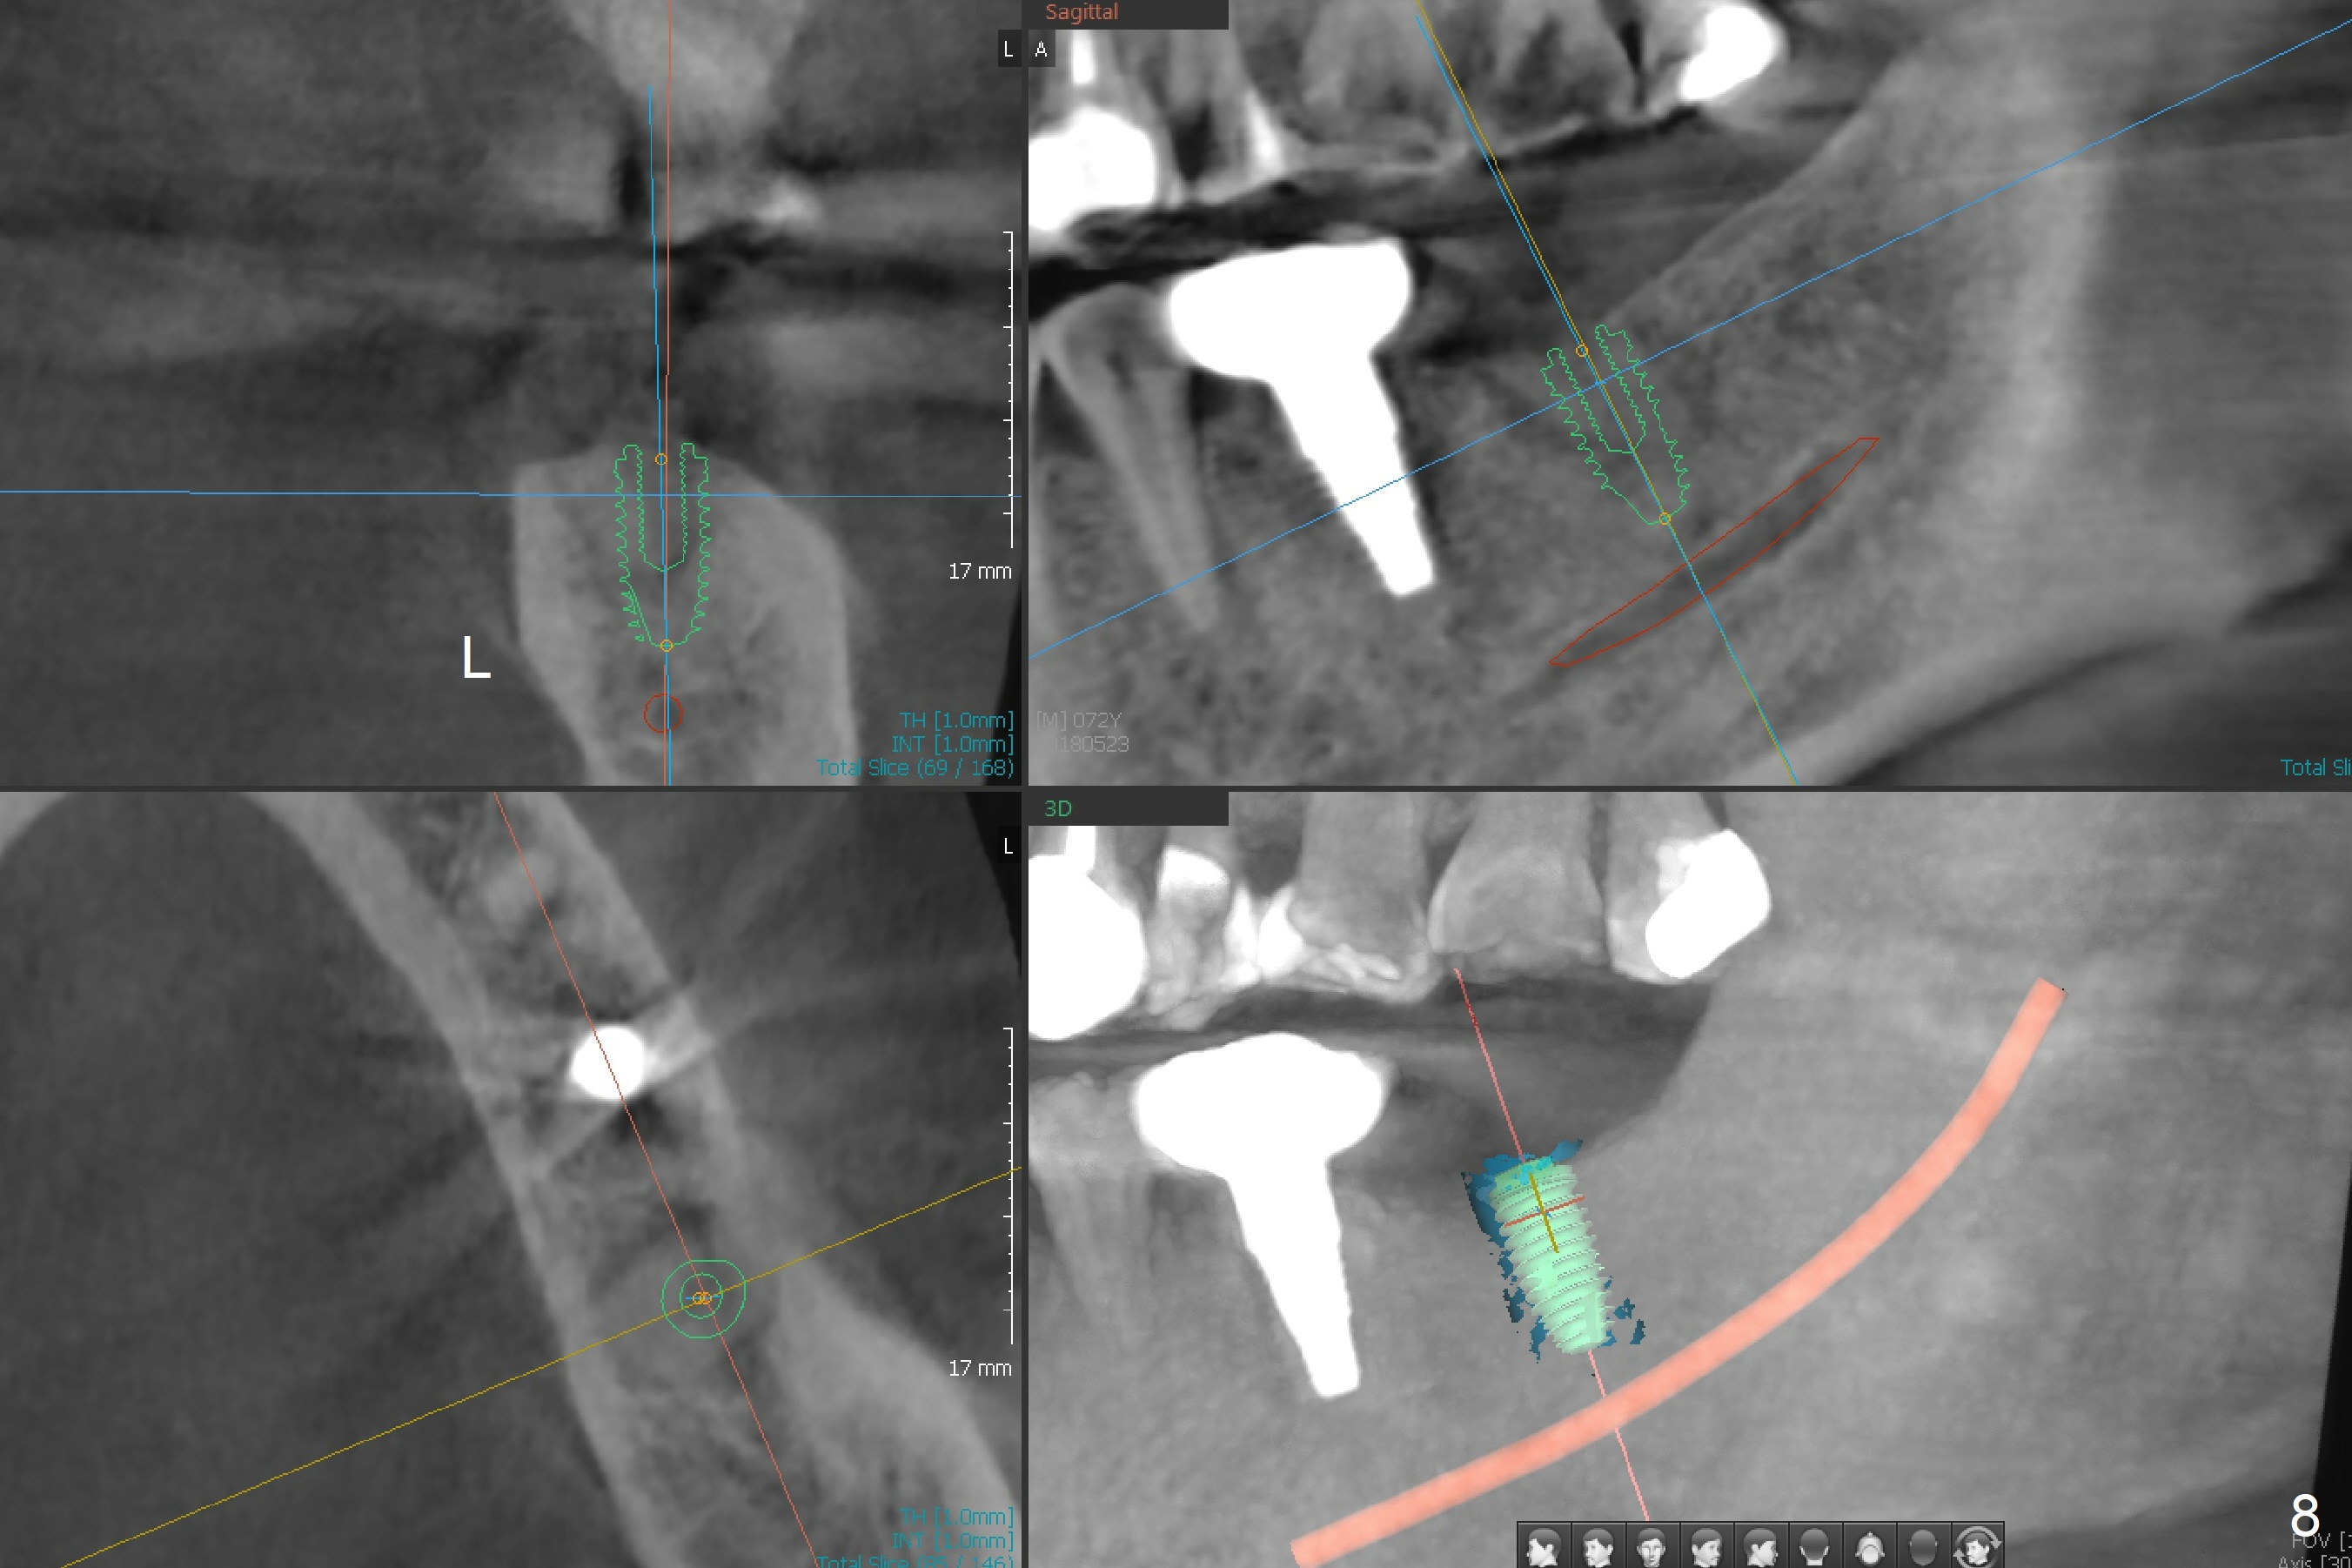

Due to severe furca (Fig.1 *) and distal root (Fig.2 D) infection at #31, there is pain when osteotomy is initiated in the apical native bone for 2 mm after extraction (Fig.3). The distal root is found to have vertical fracture. Socket preservation is performed with Vera Graft, collagen plug and 6-month membrane (Fig.4). In fact it would be possible to initiate osteotomy (Fig.5 white line) in the mesial slope (red dashed line) for implant placement (less infection (far from the lesion), less pain). There is postop pain and swelling, but the symptoms are less 7 days postop (Fig.6). The patient returns 6 months post socket preservation (Fig.7). The bone density at the healed socket is high (>1000 units); a 5x10 mm implant will be placed with guide (Fig.8). After implant placement at #18, make a buccal incision to explore the buccal gingival defect at #19 (Fig.9, 1), most likely due to extra bone graft.